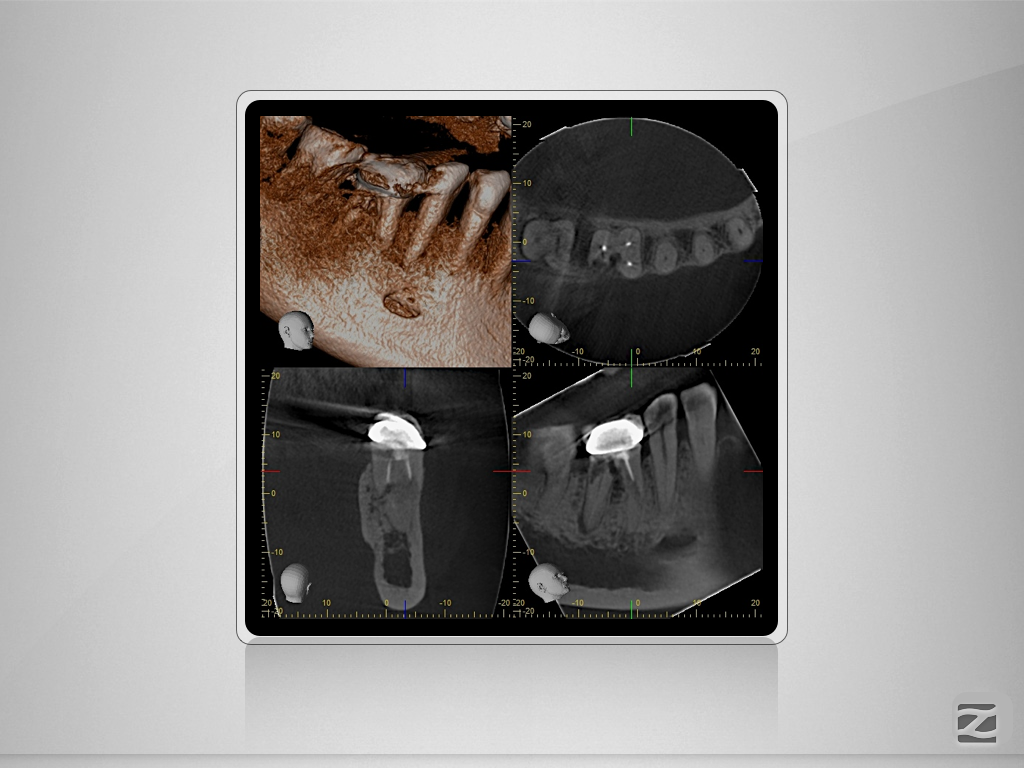

46D.008

2D vs. 3D (XXVIV)